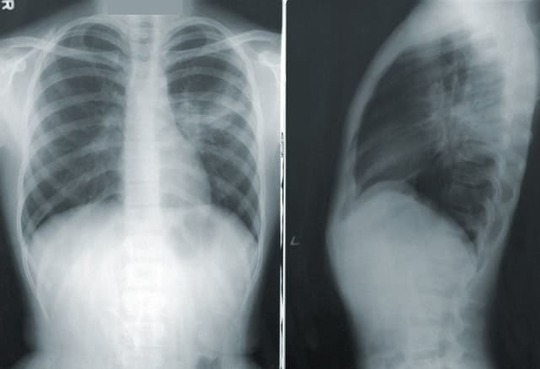

ある日、50歳の男性が風邪のような症状と息苦しさで当クリニックを訪れました。彼は以前に健康問題を抱えておらず、体調の急変に驚いていました。彼の体温は38.5度で、急速な呼吸と苦痛を伴う咳を伴っていました。彼の片方の肺で呼吸音が減少していることがわかり、さらに胸部X線画像により、彼の肺の一部に液体の蓄積が確認されました。その結果、彼は胸膜炎と判断されました。

判断の確認と感染原因の特定のために、胸水のサンプルを採取するための手術的な手順、すなわち胸腔穿刺が行われました。この手順は局所麻酔下で行われ、液体を胸腔から抽出するための細い針が胸壁に挿入されます。

その後、抽出された胸水を調査し、感染の原因を特定するための細菌培養が行われました。培養結果から、彼が肺炎球菌による感染を発症していることが明らかになりました。そのため、彼には即座に適切な抗生物質が投与され、痛みと炎症を抑えるために非ステロイド性抗炎症薬も処方されました。

また、胸水が再度溜まるのを防ぐため、彼の胸腔には一時的なチューブが挿入され、余分な液体が体外に排出されるようにしました。この改善方法は彼の症状を大幅に改善し、彼の体は抗生物質による改善を受け入れ始めました。

彼は1週間ほど入院し、その間に定期的に調べ、胸水が再蓄積していないことを確認しました。その後、彼の症状は明らかに改善し、体温も正常に戻りました。胸水の排出も成功し、チューブは安全に除去されました。

その後数ヶ月にわたり、彼は定期的に当クリニックを訪れ、健康状態をチェックしました。幸いにも彼の胸膜炎は再発せず、数ヶ月後の胸部X線では正常な結果が戻ってきました。